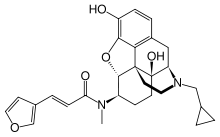

The pharmacodynamic response to an opioid depends upon the receptor to which it binds, its affinity for that receptor, and whether the opioid is an agonist or an antagonist. For example, the supraspinal analgesic properties of the opioid agonist morphine are mediated by activation of the μ1 receptor; respiratory depression and physical dependence by the μ2 receptor; and sedation and spinal analgesia by the κ receptor. Each group of opioid receptors elicits a distinct set of neurological responses, with the receptor subtypes (such as μ1 and μ2 for example) providing even more [measurably] specific responses. Unique to each opioid is its distinct binding affinity to the various classes of opioid receptors (e.g. the μ, κ, and δ opioid receptors are activated at different magnitudes according to the specific receptor binding affinities of the opioid). For example, the opiate alkaloid morphine exhibits high-affinity binding to the μ-opioid receptor, while ketazocine exhibits high affinity to ĸ receptors. It is this combinatorial mechanism that allows for such a wide class of opioids and molecular designs to exist, each with its own unique effect profile. Their individual molecular structure is also responsible for their different duration of action, whereby metabolic breakdown (such as N-dealkylation) is responsible for opioid metabolism.

Several semi-synthetic opioids were developed in Germany in the 1910s. The first, oxymorphone, was synthesized from thebaine, an opioid alkaloid in opium poppies, in 1914.[228] Next, Martin Freund and Edmund Speyer developed oxycodone, also from thebaine, at the University of Frankfurt in 1916.[229] In 1920, hydrocodone was prepared by Carl Mannich and Helene Löwenheim, deriving it from codeine. In 1924, hydromorphone was synthesized by adding hydrogen to morphine. Etorphine was synthesized in 1960, from the oripavine in opium poppy straw. Buprenorphine was discovered in 1972.[228]

- Buprenorphine—partial agonist